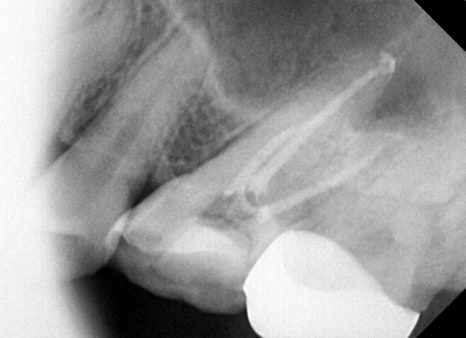

잇몸치료와 충치치료가 완료된 사진입니다.

치아 사이 충치가 생긴 어금니는 충치가 깊어 신경치료까지 진행했습니다.

잇몸 경계 부위 충치로 인해 치료 과정에서 잇몸에 출혈이 약간 있을 수밖에 없지만

금방 회복되며, 앞니 쪽이라 기존 치아의 색상에 맞춰

레진 치료를 이쁘게 진행해 드렸습니다.^^